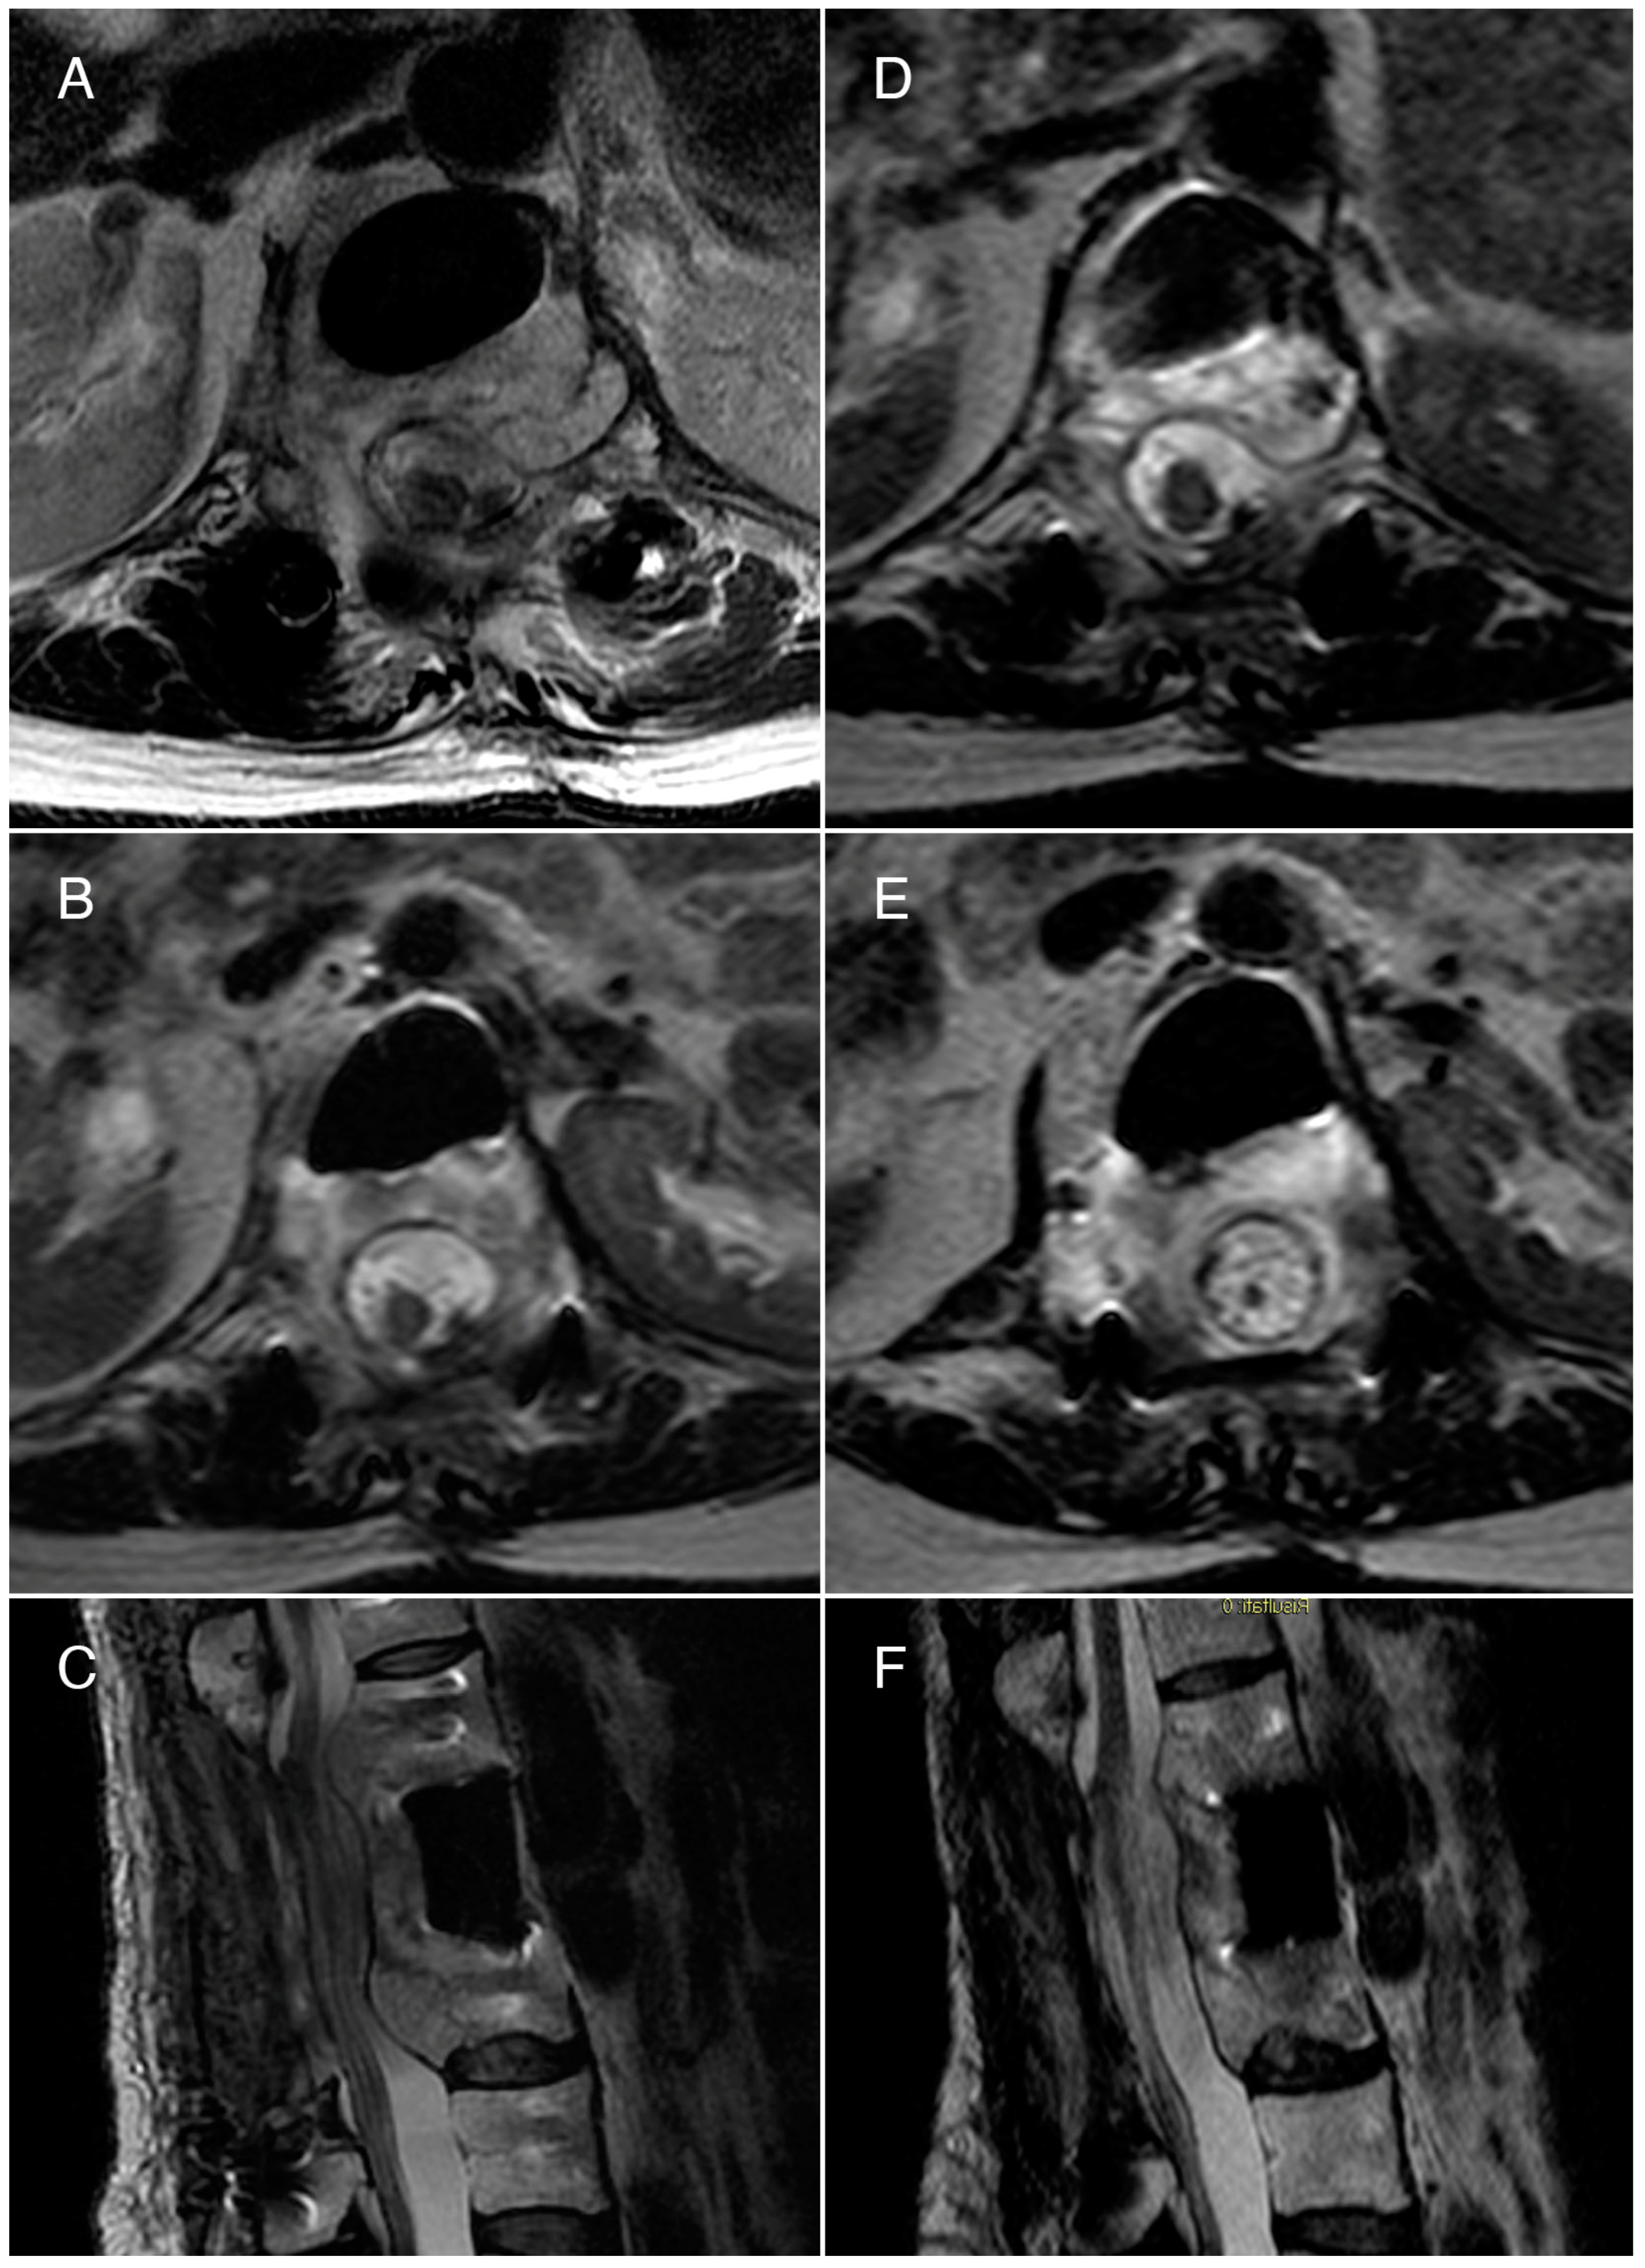

3.1. Case 1

3.2. Case 2